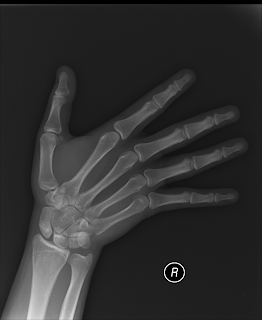

i was in the pool at the xmas party, it was snowing, i got out the pool, the stairs were iced, i slipped... fell on my wrist, broke the ligament joining the thumb 2 the wrist!

i had x-rays & a MRI

for the surgery, they knocked me out with a general anesthetic, cut my wrist open, stretched out the bones in my wrist & screwed a long screw that extends across my whole wrist & sticks out on both sides!

8weeks healing time & they say i will need therapy 2 learn how 2 use my thumb again!